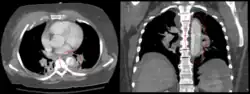

-

Aortic dissection -

CT with contrast demonstrating aneurysmal dilation and a dissection of the ascending aorta (type A Stanford) -

Chest CT with descending (type B Stanford) aortic dissection (red circle)

Type A dissection with pericardial effusion as a result.